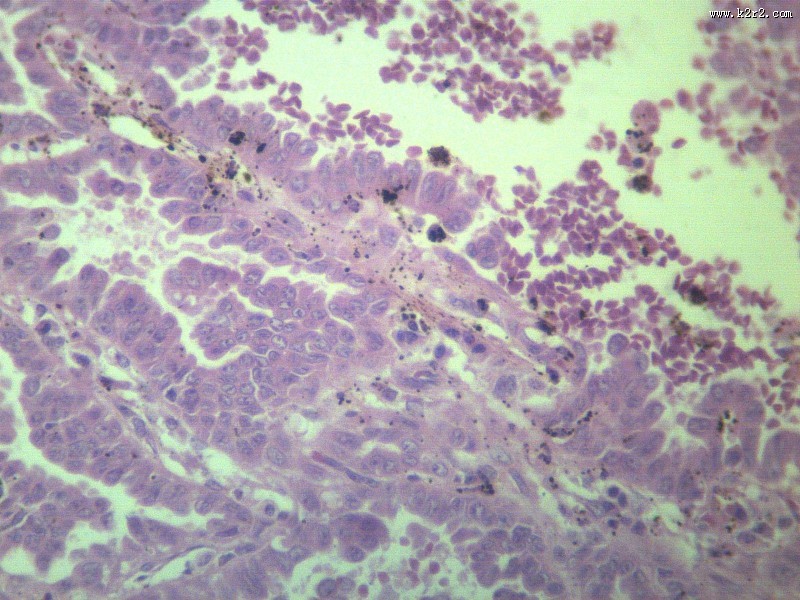

腺癌 - 第10张

腺癌

腺癌肝转移大全

显微切片

肿瘤

adenocarcinoma